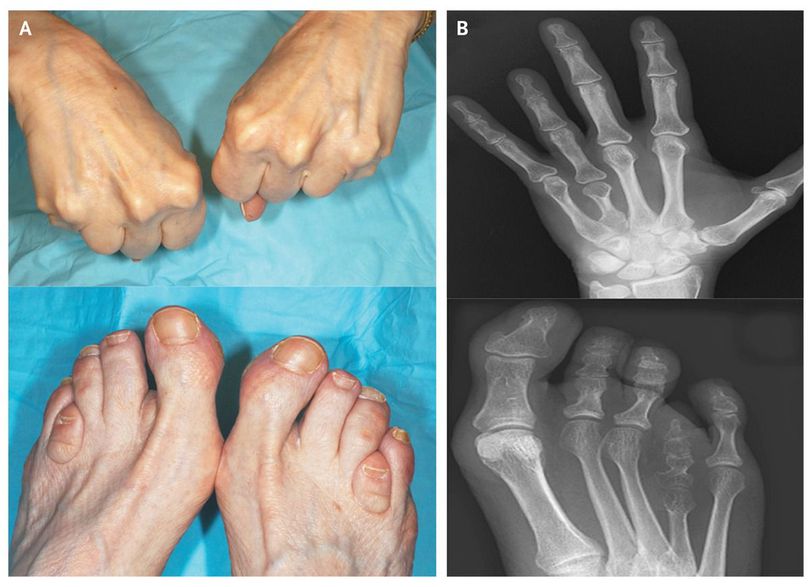

A 71-year-old woman presented to the clinic for management of hypertension. On physical examination, she was found to have an absence of the fourth knuckle on each hand and brachymetatarsia of the fourth toes (Panel A). She had no cognitive deficits or dysmorphic features. Serum measurements of calcium, phosphorus, and parathyroid hormone were normal. Radiography of the hands and feet showed fourth metacarpal and metatarsal shortening along with osteodystrophic features (Panel B), a condition that was diagnosed as Albright's hereditary osteodystrophy. First described in 1952 by Fuller Albright, the disorder is caused by a paternally transmitted mutation in the gene encoding adenylate cyclase-stimulating G alpha protein (GNAS1), which results in the characteristic osteodystrophy with a normal renal response to parathyroid hormone and preserved calcium homeostasis (called pseudopseudohypoparathyroidism). Maternal transmission of the same gene creates a different phenotype, in which the same anatomical abnormalities are seen but there is resistance to parathyroid hormone with hypocalcemia, hyperphosphatemia, and high serum levels of parathyroid hormone (called pseudohypoparathyroidism). Patients with pseudopseudohypoparathyroidism usually do not need specific treatment or further follow-up.